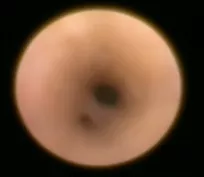

canal salivaire vue endoscopique |